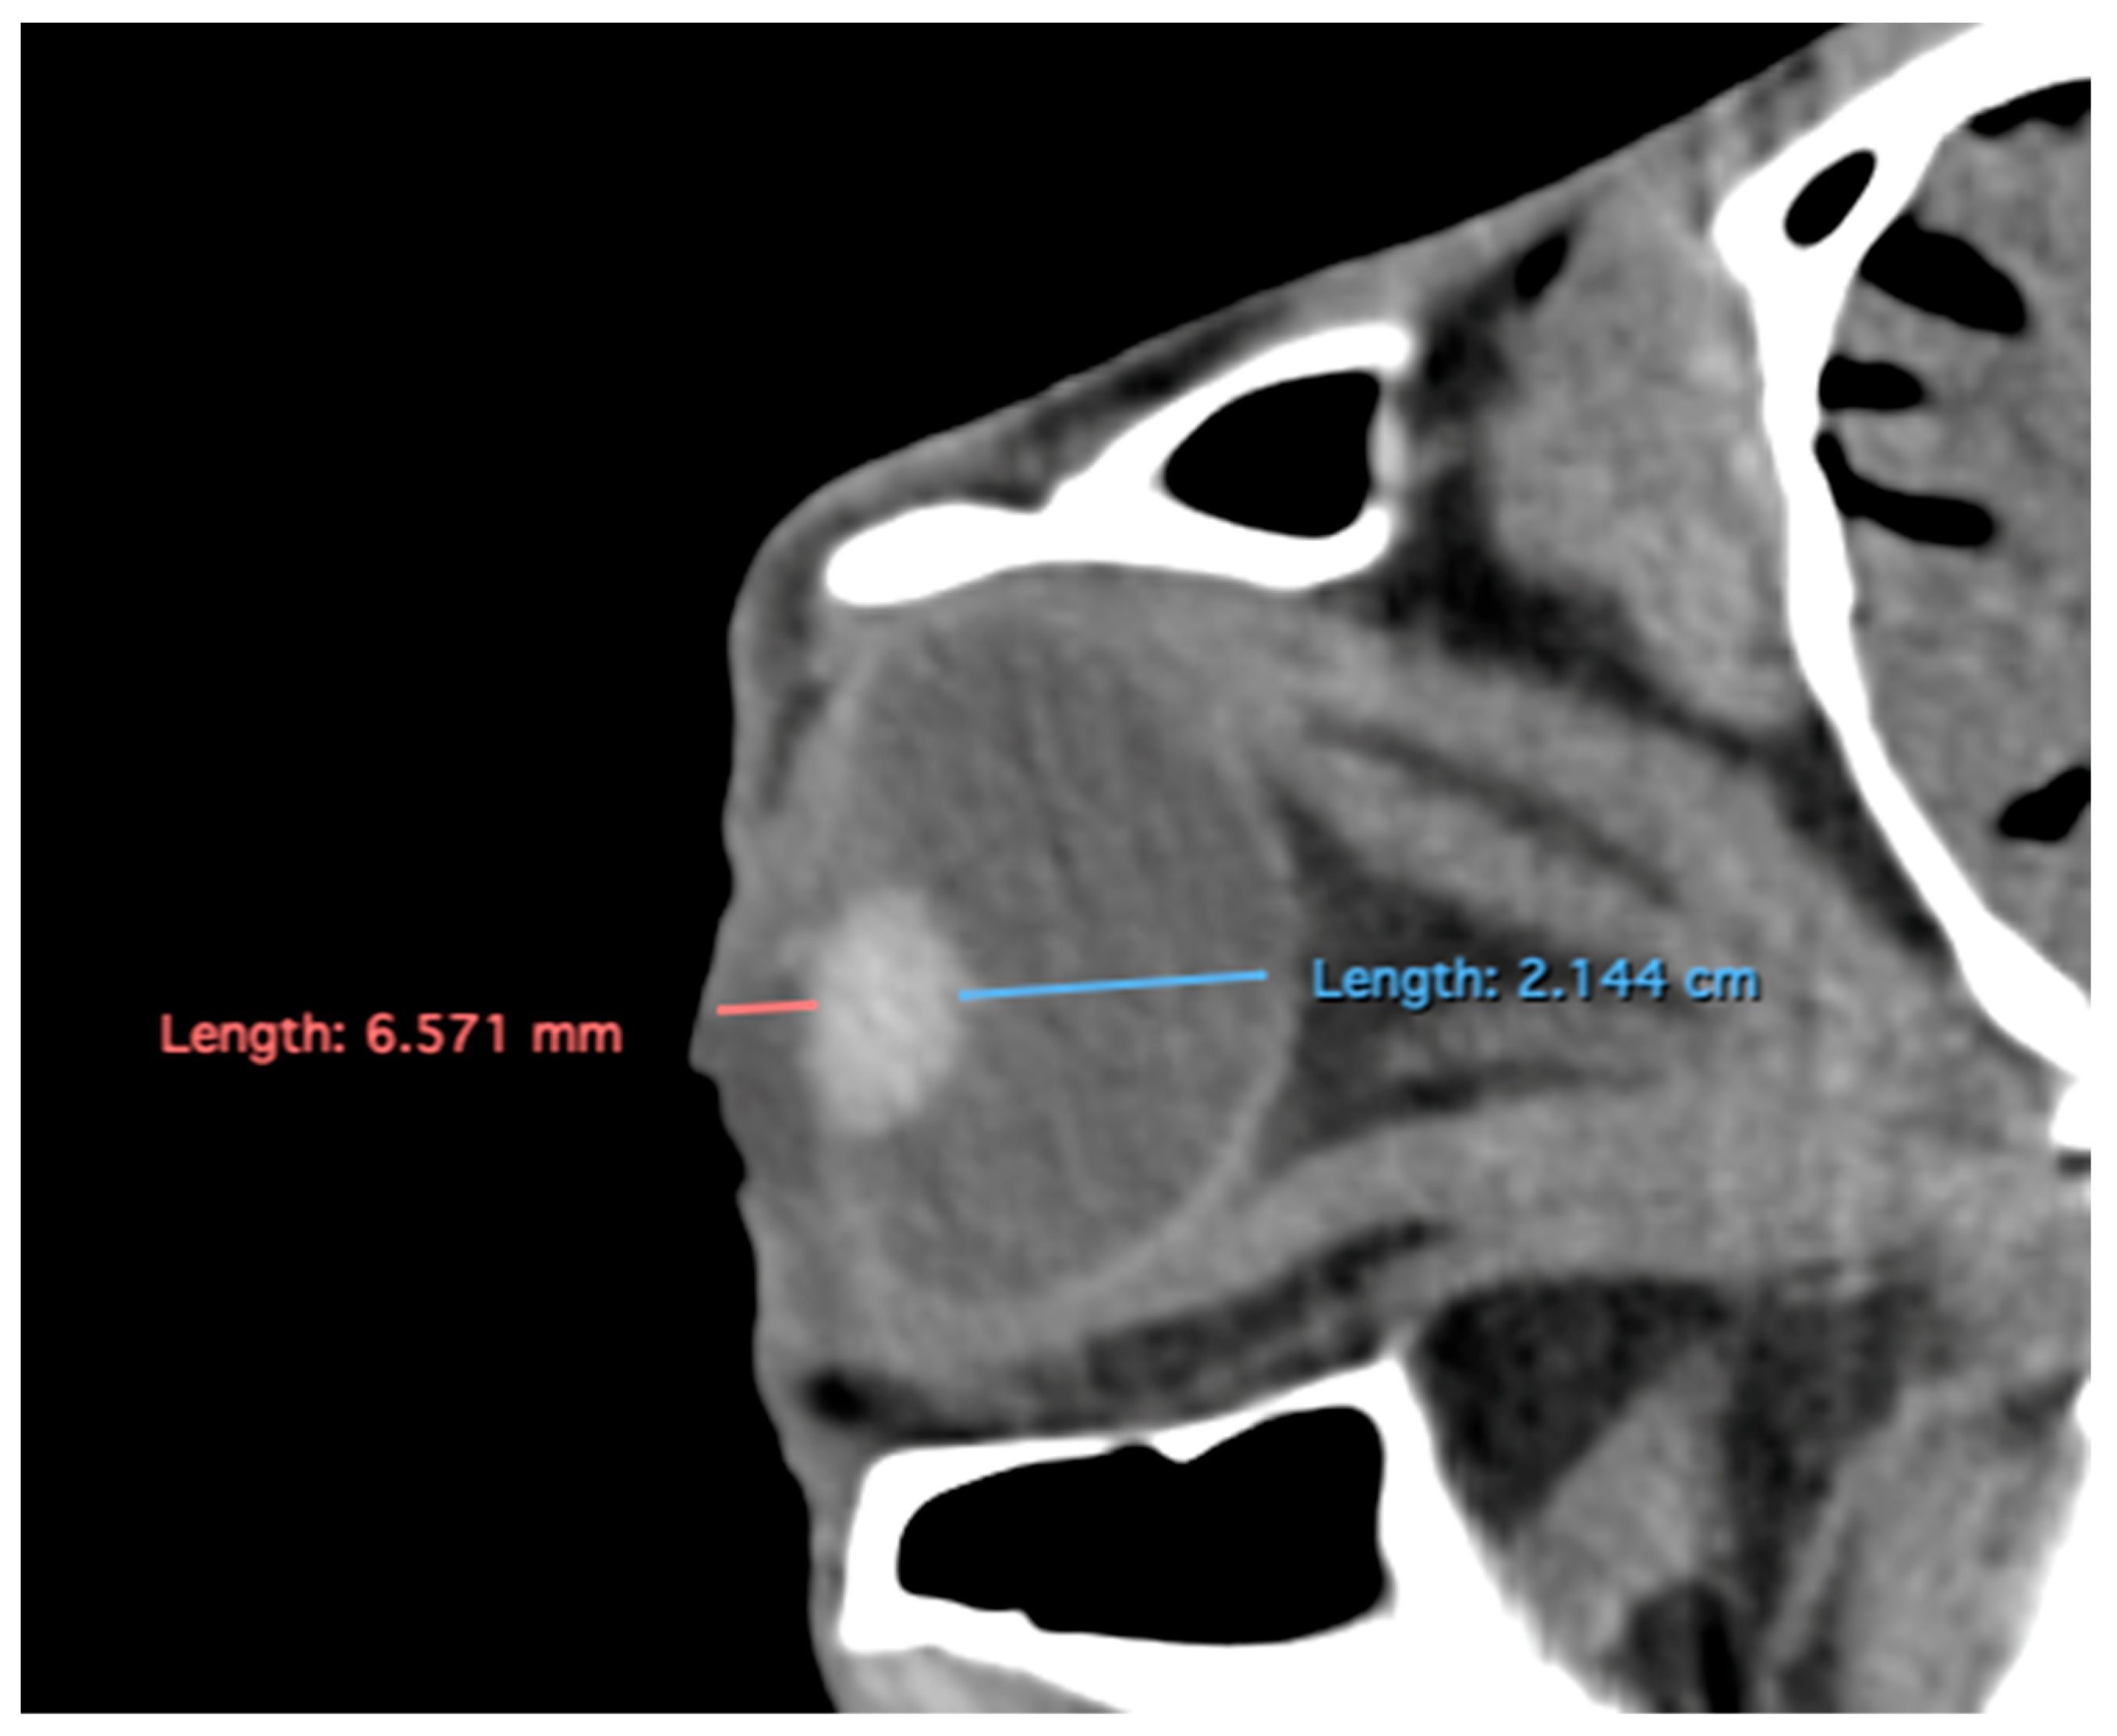

Figure 4.

Parasagittal multiplanar reconstruction (MPR) images of the equine eyeball showing (A) eyeball length and (B) the maximal antero-posterior distance of the lens measured along its midline.

- Lens rostrocaudal length: Maximum anteroposterior distance of the lens measured along its midline (Figure 4B).

- Eyeball rostrocaudal length: Maximal anteroposterior distance of the eyeball from the internal surface of the cornea to the internal surface of the choroid/retina/sclera (Figure 4A).